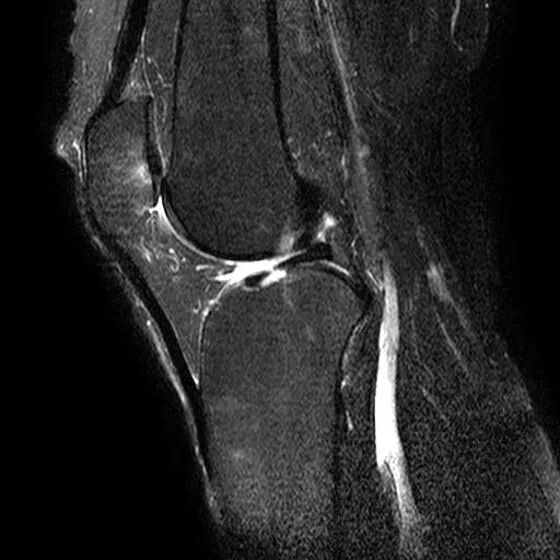

1、宽度减小,在通过半月板体部的冠状面上蝶形消失,同时可见内移的半月板位于髁间窝、交叉韧带旁2、矢状面示残余的前角或后角变小或截断3、半月板前(后)角增宽或双半月板前(后)角征4、双前交叉韧带或双后交叉韧带征

桶柄状撕裂:宽度减小,在通过半月板体部的冠状面上蝶形消失,同时可见内移的半月板位于髁间窝、交叉韧带旁

桶柄状撕裂:半月板后角增宽